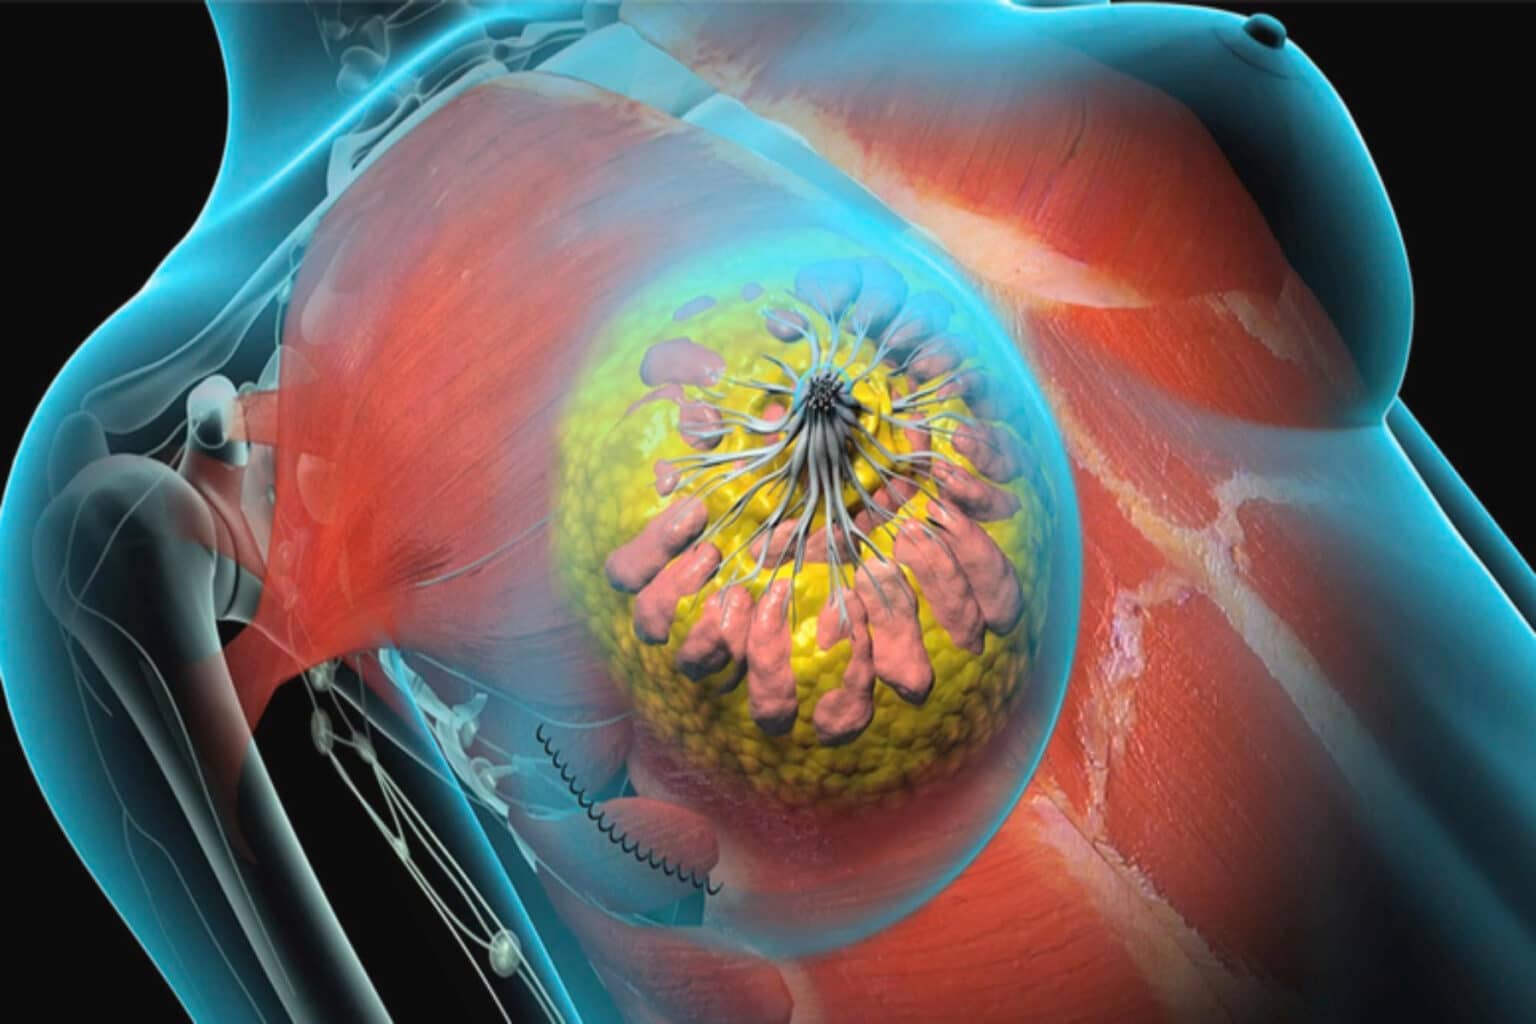

Καρκίνος του μαστού